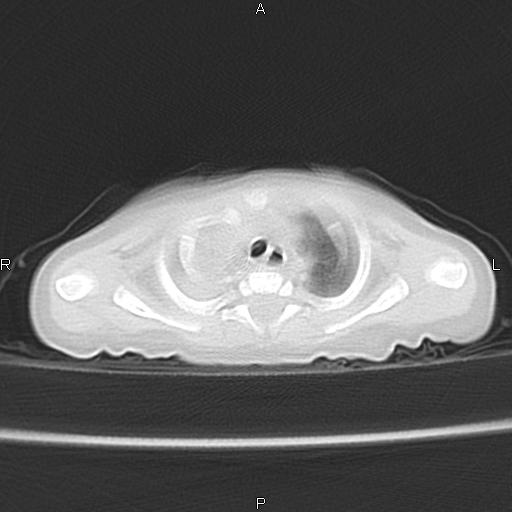

以下是引用aa13877358820在2010-7-26 12:35:00的发言:[br]男性,三个月,卧位胸片,咳嗽、气促、发热14天,两肺闻及细小水泡音。[br]